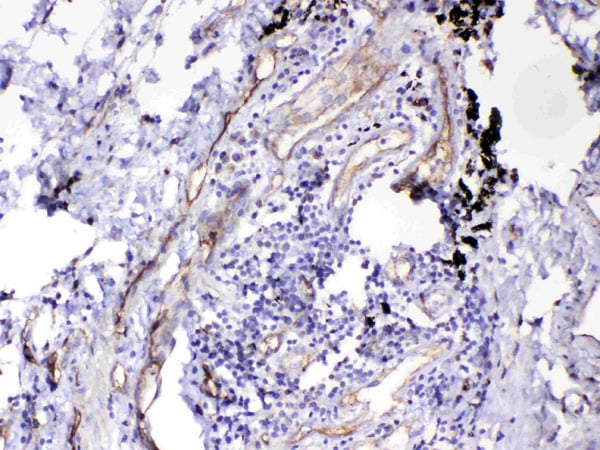

IHC (Immunohistochemisry)

(Figure 3. IHC analysis of HOMER3 using anti-HOMER3 antibody (AAA124742).HOMER3 was detected in paraffin-embedded section of human lung cancer tissue. Heat mediated antigen retrieval was performed in citrate buffer (pH6, epitope retrieval solution) for 20 mins. The tissue section was blocked with 10% goat serum. The tissue section was then incubated with 1ug/ml rabbit anti-HOMER3 Antibody (AAA124742) overnight at 4 degree C. Biotinylated goat anti-rabbit IgG was used as secondary antibody and incubated for 30 minutes at 37 degree C. The tissue section was developed using Strepavidin-Biotin-Complex (SABC) with DAB as the chromogen.)